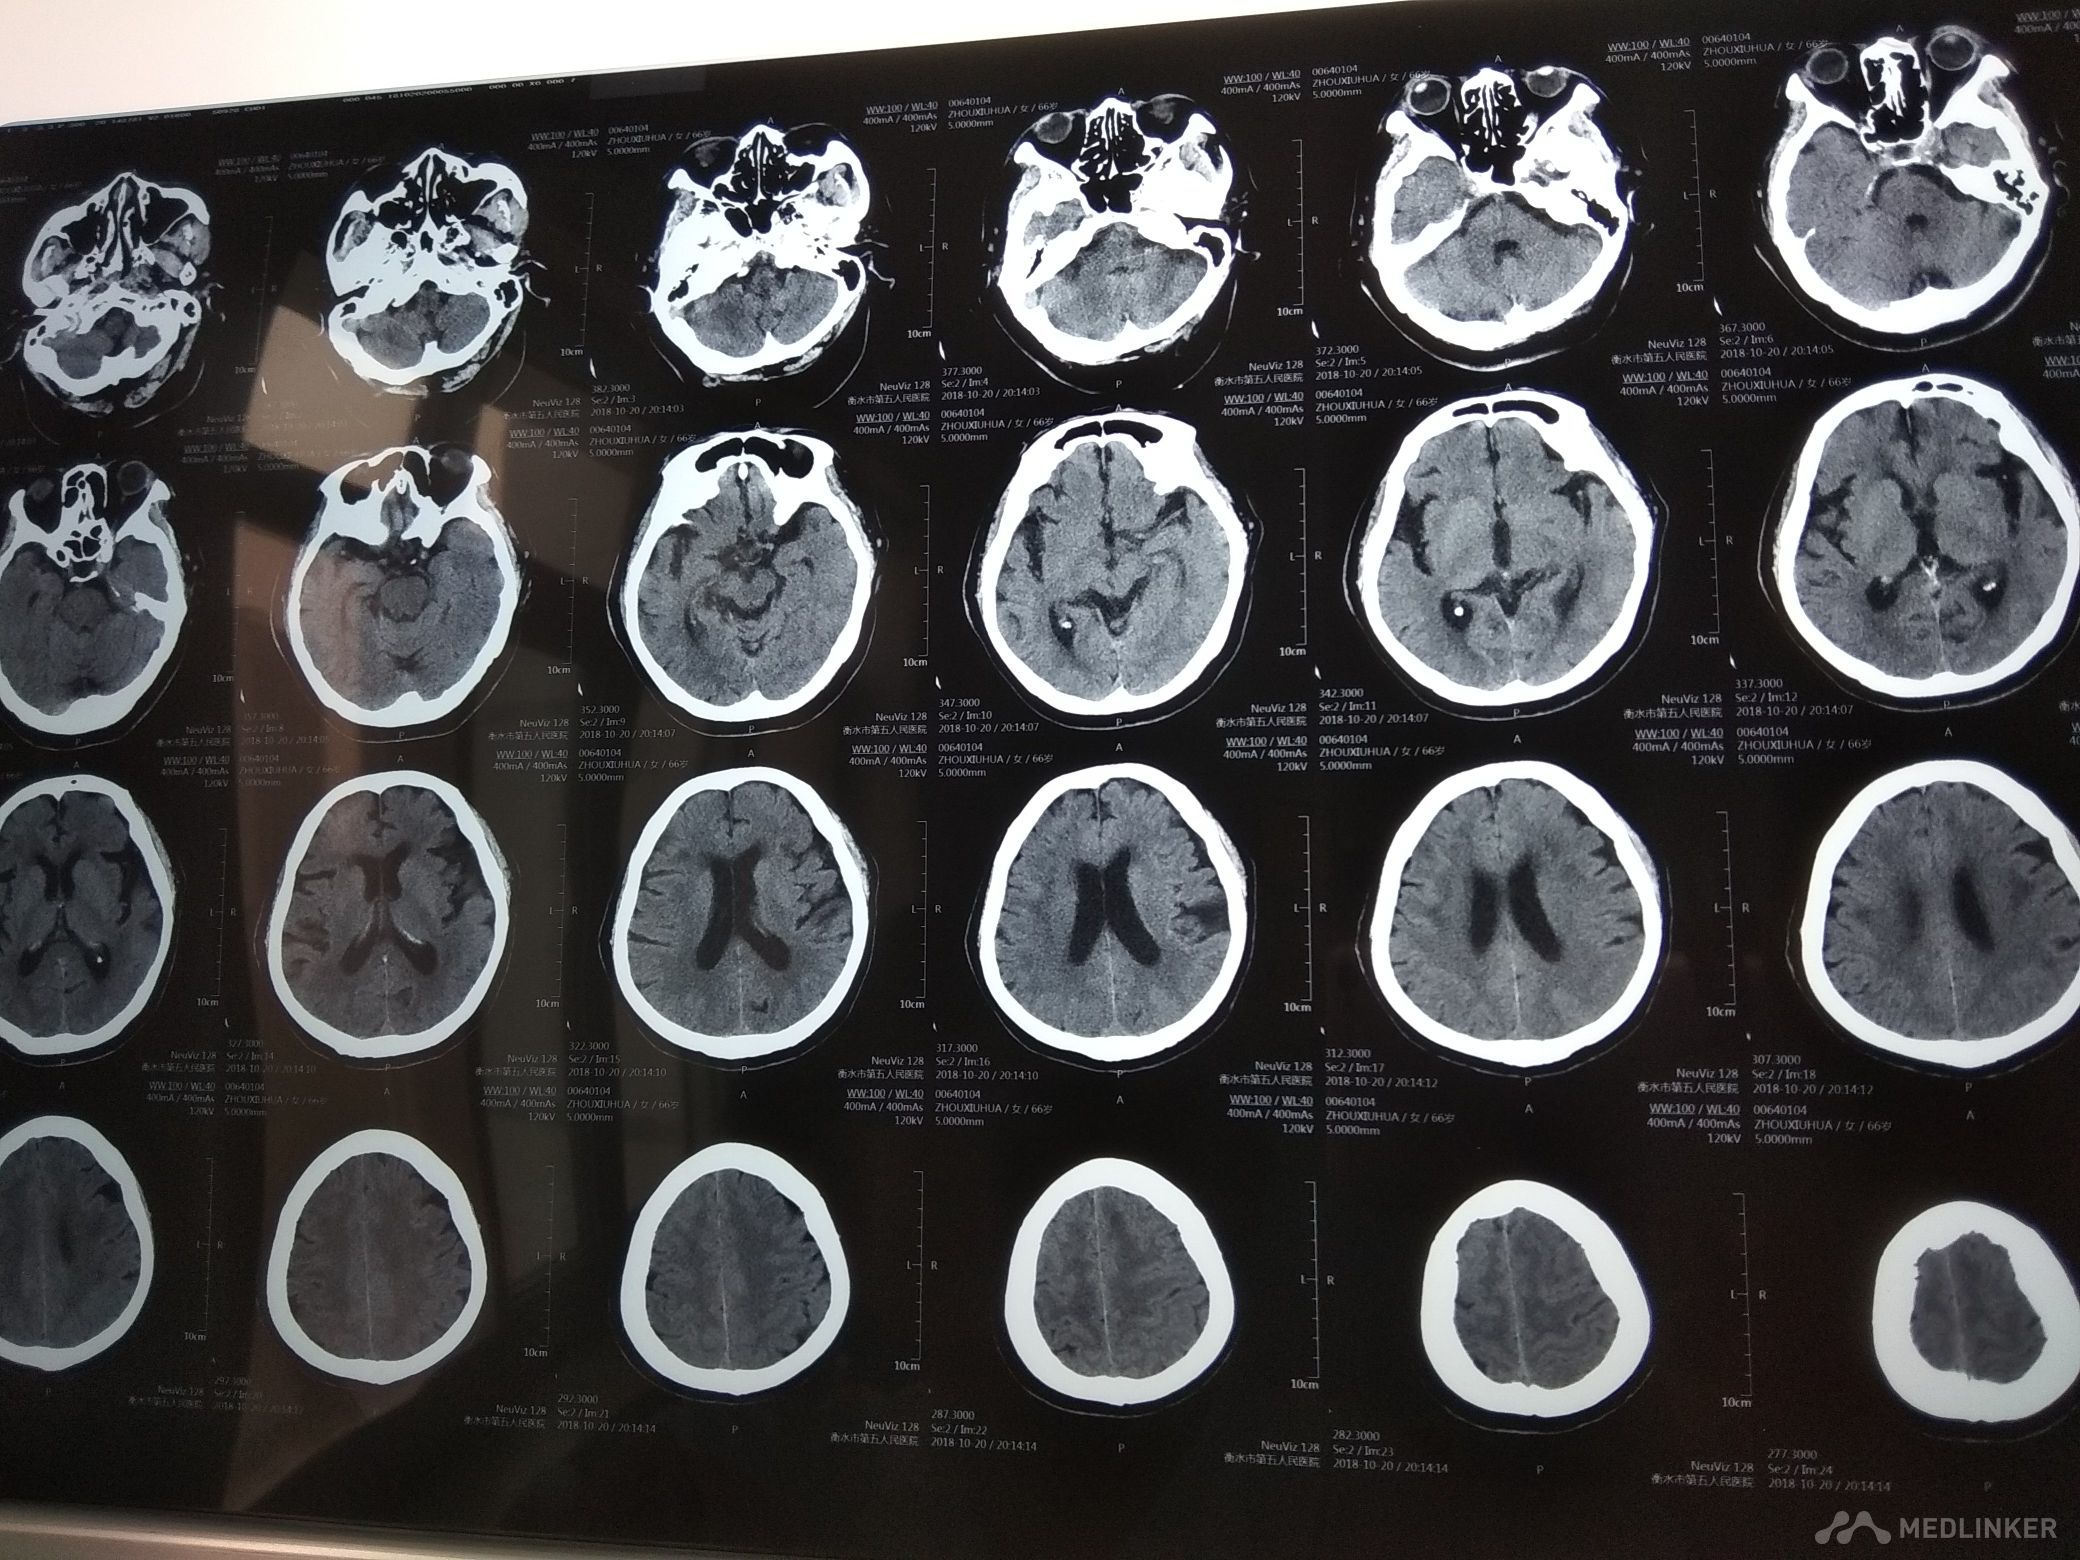

主诉 发作性左侧肢体麻木无力2天。病史 59岁男性患者,于入院前2天无明显诱因出现左侧肢体麻木无力,左下肢明显,走路拖地,左上肢持物不稳。未予治疗,约10余分钟缓解。无头晕头痛,无恶心呕吐,无肢体抽搐,无意识障碍,无尿便障碍。共发作1次,,为求诊治,遂来我院,以“短暂性脑缺血发作”收入我科。 既往高血压病史,最高210/100mmHg,平时未服药。吸烟饮酒史。 。

查体BP180/90mmHg,神清,语利,右利手,计算力,记忆力,定向力,理解判断力正常。鼻唇沟基本对称,伸舌基本居中,四肢肌力5级,肌张力,腱反射适中对称,针刺觉.共济检查正常,双侧病理征未引出。颈软,双下肢无水肿。肺心腹未见明显异常。 心电图大致正常 化验结果:血常规,血凝,电解质,肝肾功能,心肌酶,同型半胱氨酸正常。血脂TG1.93mmol/L,密切观察病情变化

诊断 短暂性脑缺血发作,高血压3级 很高危,2型糖尿病,高脂血症。 治疗 予阿司匹林抗血小板聚集,降脂稳定斑块,促进侧支循环建立,改善循环,营养神经,降糖调压等治疗。